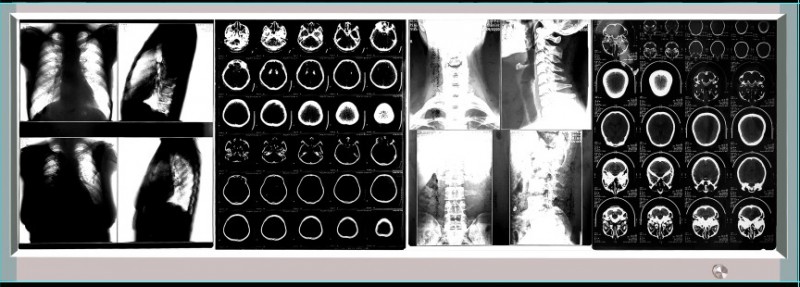

LED单联观片灯 LED双联观片灯 LED三联观片灯 LED四联观片灯

四联LED观片灯 四联LED观察灯 四联LED读片灯 四联LED阅片灯

四联LED观片灯,LED调光插片观片灯